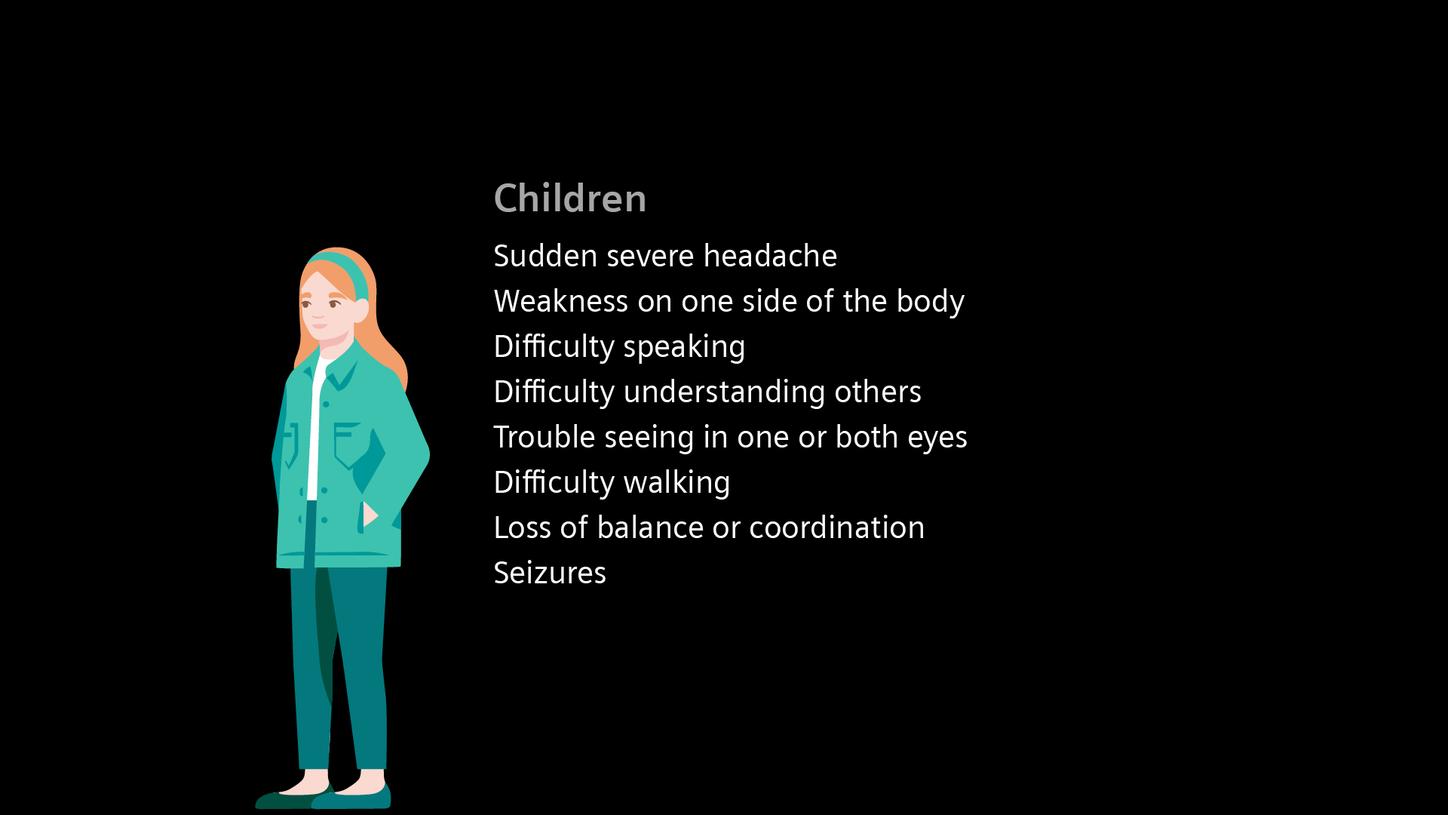

Recognizing early warning signs – FAST

The sooner treatment begins after the onset of stroke symptoms, the better the chance of preventing permanent damage. Recognizing early warning signs – like sudden weakness or numbness on one side, slurred speech, or vision disturbances – can be life-saving. The easy to remember FAST test (Face, Arms, Speech, Time) provides a quick and effective way to identify a potential stroke and act immediately.